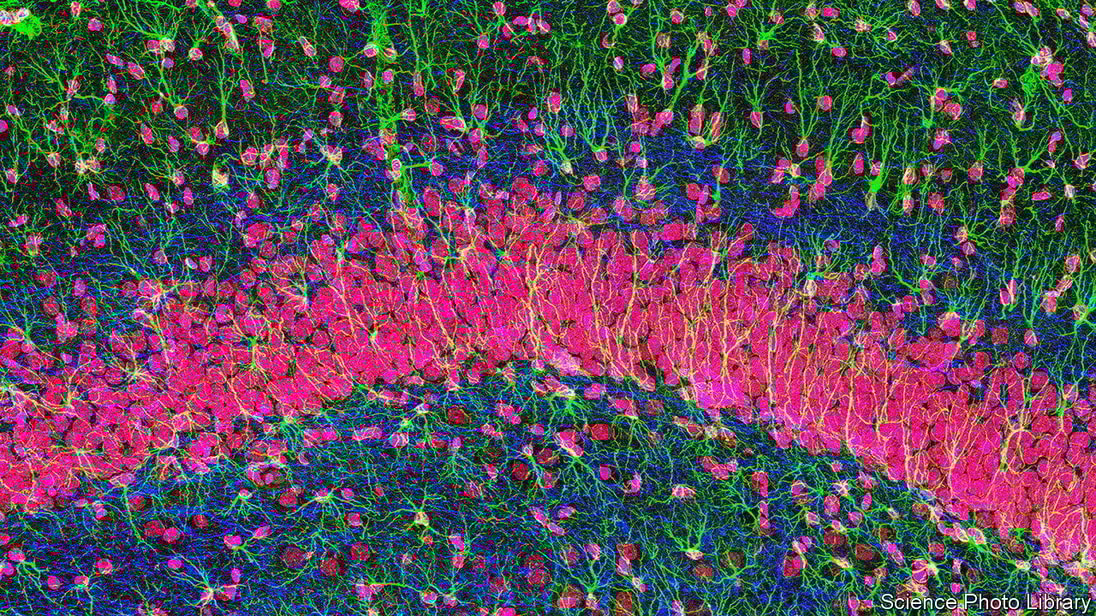

Το διανοητικό έργο υποστηρίζουν και άλλοι τρεις τύποι κυττάρων, με σημαντικές ιδιότητες που μέχρι πρόσφατα μας ήταν άγνωστες: τα μικρογλοία, τα αστροκύτταρα και οι ολιγοδενδρίτες.

Τα νευρογλοιακά κύτταρα, όπως ονομάζονται στο σύνολό τους, είχαν ελαφρώς παραμεληθεί από την επιστήμη της νευρολογίας, αλλά αυτό έχει πλέον αλλάξει αφού οι ερευνητές συνειδητοποίησαν πως δεν λειτουργούν απλώς ως εγκεφαλική «κόλλα».

Τα μικρογλοία λειτουργούν ως «κηπουροί» της σκέψης. «Κλαδεύουν» τους συνδέσμους μεταξύ των νευρώνων για να διατηρήσουν το δίκτυο σε τάξη. Οι ολιγοδενδρίτες, που επί μακρόν απορρίπτονταν ως απλοί «μονωτές» των ηλεκτρικά αγώγιμων ινών μέσω των οποίων επικοινωνούν οι νευρώνες, παίζουν κρίσιμο ρόλο στη ρύθμιση των σημάτων. Και τα αστροκύτταρα, τα πιο ενδιαφέροντα από όλα, μετατρέπουν τις συνάψεις σε βιολογικά «τρανζίστορ», ρυθμίζοντας τη ροή των πληροφοριών στις διασταυρώσεις των αξόνων που μεταφέρουν τα σήματα.